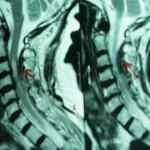

A previously healthy 65 year old female presented to us with the complaint of right side hemiplegia without any significant history of trauma. On subsequent inquiry she gave a history of brisk involuntary hyperextension of the neck following which she developed sudden onset hemiparesis, progressed to hemiplegia within a span of five days. The patient was neither diabetic, hypertensive nor on antiplatelet/anticoagulant therapy. She did not have a history of any congenital or acquired disorder of coagulation. On elaborate neurological survey it was found that motor power of the patient’s right side upper and lower limb was of grade 0/5 with anesthesia of left side below C3. The patient had spasticity with hyperreflexia and extensor plantar response on motor affected side. Her bladder and bowel functions were normal. She was evaluated with a cervicodorsal MRI scan, which showed a hyper intense space occupying lesion suggesting an epidural hematoma at the C3-C4 level (FIG.1). The lesion was compressing the thecal sac as well as spinal cord. The patient was taken up for emergency surgery. With the patient in prone position under general anaesthesia, a posterior midline incision was taken exposing the tips of the spinous processes from C3 to C5 levels. Two bony gutters were drilled bilaterally at the border of the exposed laminae by means of an air drill. In our case, the left side border of the laminae was excised from its cranial to caudal end with a kerison rongeur and the spinous processes and the laminae were pushed laterally as if to open a door, thereby exposing the spinal canal (Hirabayashi’s open door laminoplasty) [2]. Blood clot was found within the epidural space, which was evacuated. Histopathological examination of the evacuated material confirmed hematoma. Postoperatively the patient was immobilized with a hard cervical collar and physiotherapy (passive mobilization) was started. Four months following the surgery the patient regained her motor strength to grade 3/5 with partial return of sensory functions. At twelve months follow up motor power of the affected side improved to grade 5/5 with regaining of normal sensory functions on opposite side.